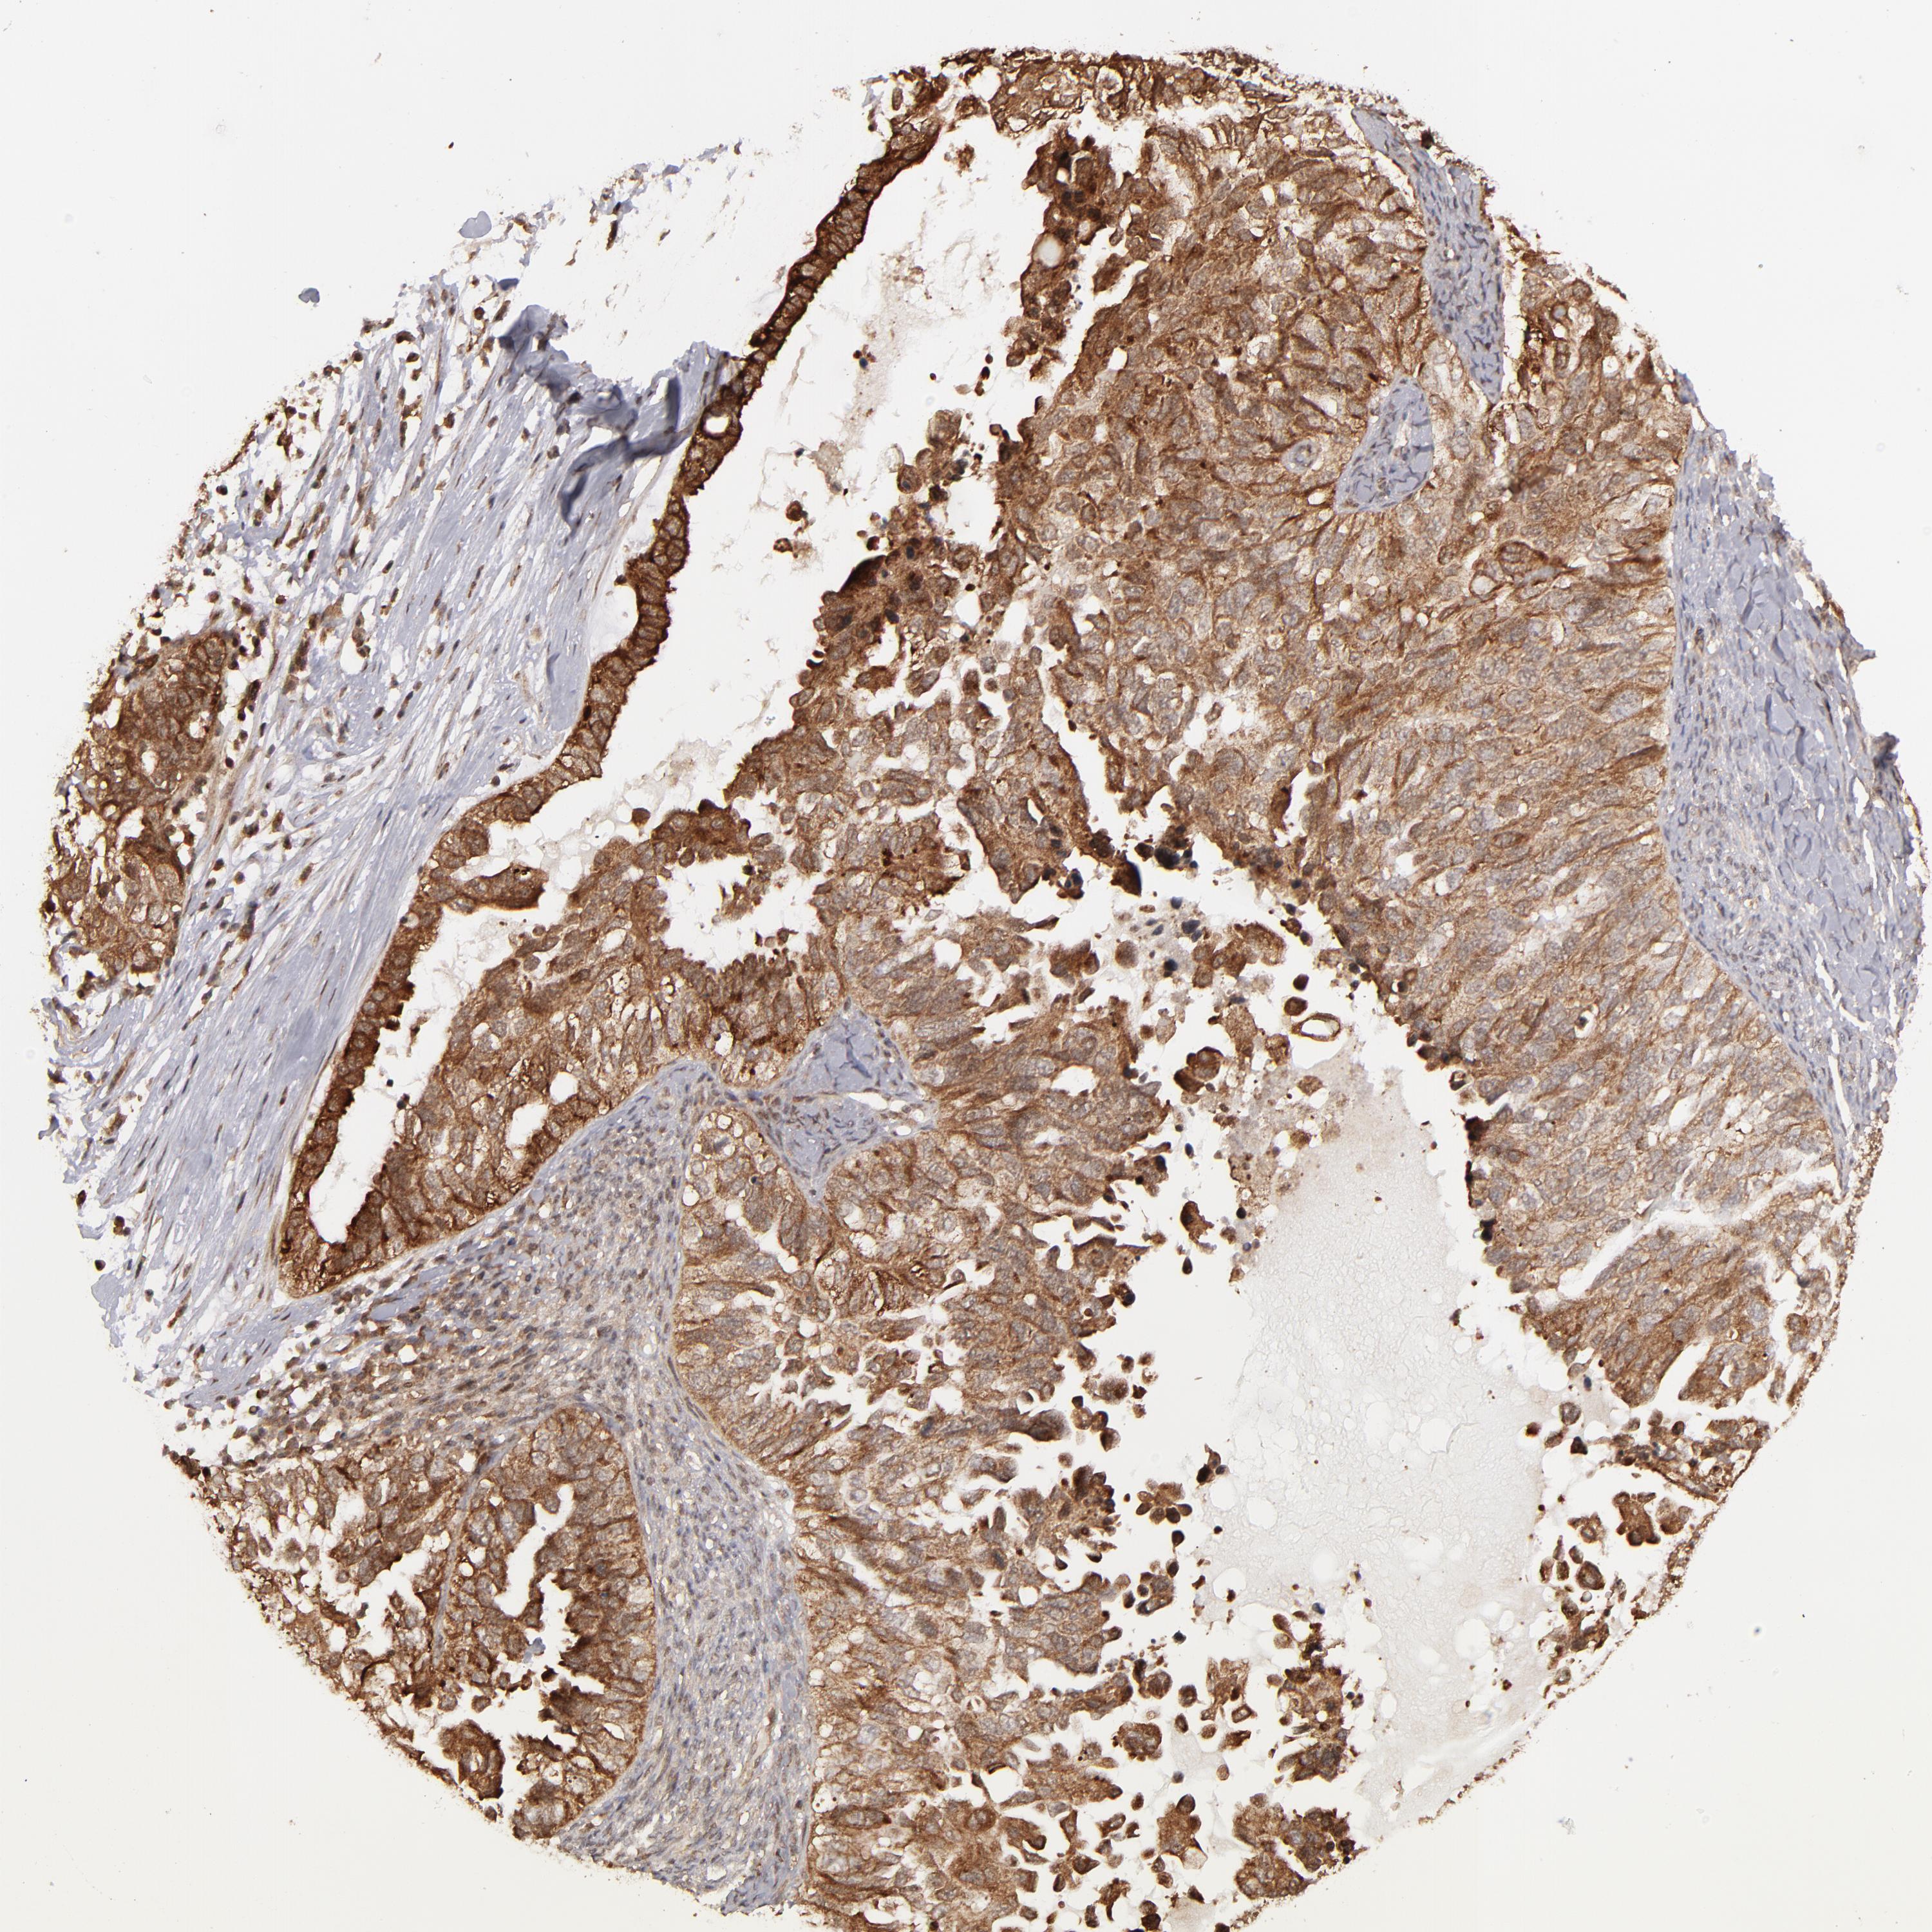

OVARIAN CANCER - Protein expressioni

A mouse-over function shows sample information and annotation data. Click on an image to view it in a full screen mode. Samples can be filtered based on level of antibody staining by selecting one or several of the following categories: high, medium, low and not detected. The assay and annotation is described here.

Note that samples used for immunohistochemistry by the Human Protein Atlas do not correspond to samples in the TCGA dataset.

Antibody stainingi

Antibody staining in the annotated cell types in the current human tissue is reported as not detected, low, medium, or high, based on conventional immunohistochemistry profiling in selected tissues. This score is based on the combination of the staining intensity and fraction of stained cells.

Each image is clickable and will lead to virtual microscopy that enables deeper exploration of all samples and also displays staining intensity scores, fraction scores and subcellular localization as well as patient and tissue information for each sample.

Antibody HPA003067

Cystadenocarcinoma, serous, NOS

Cystadenocarcinoma, mucinous, NOS

Carcinoma, endometroid